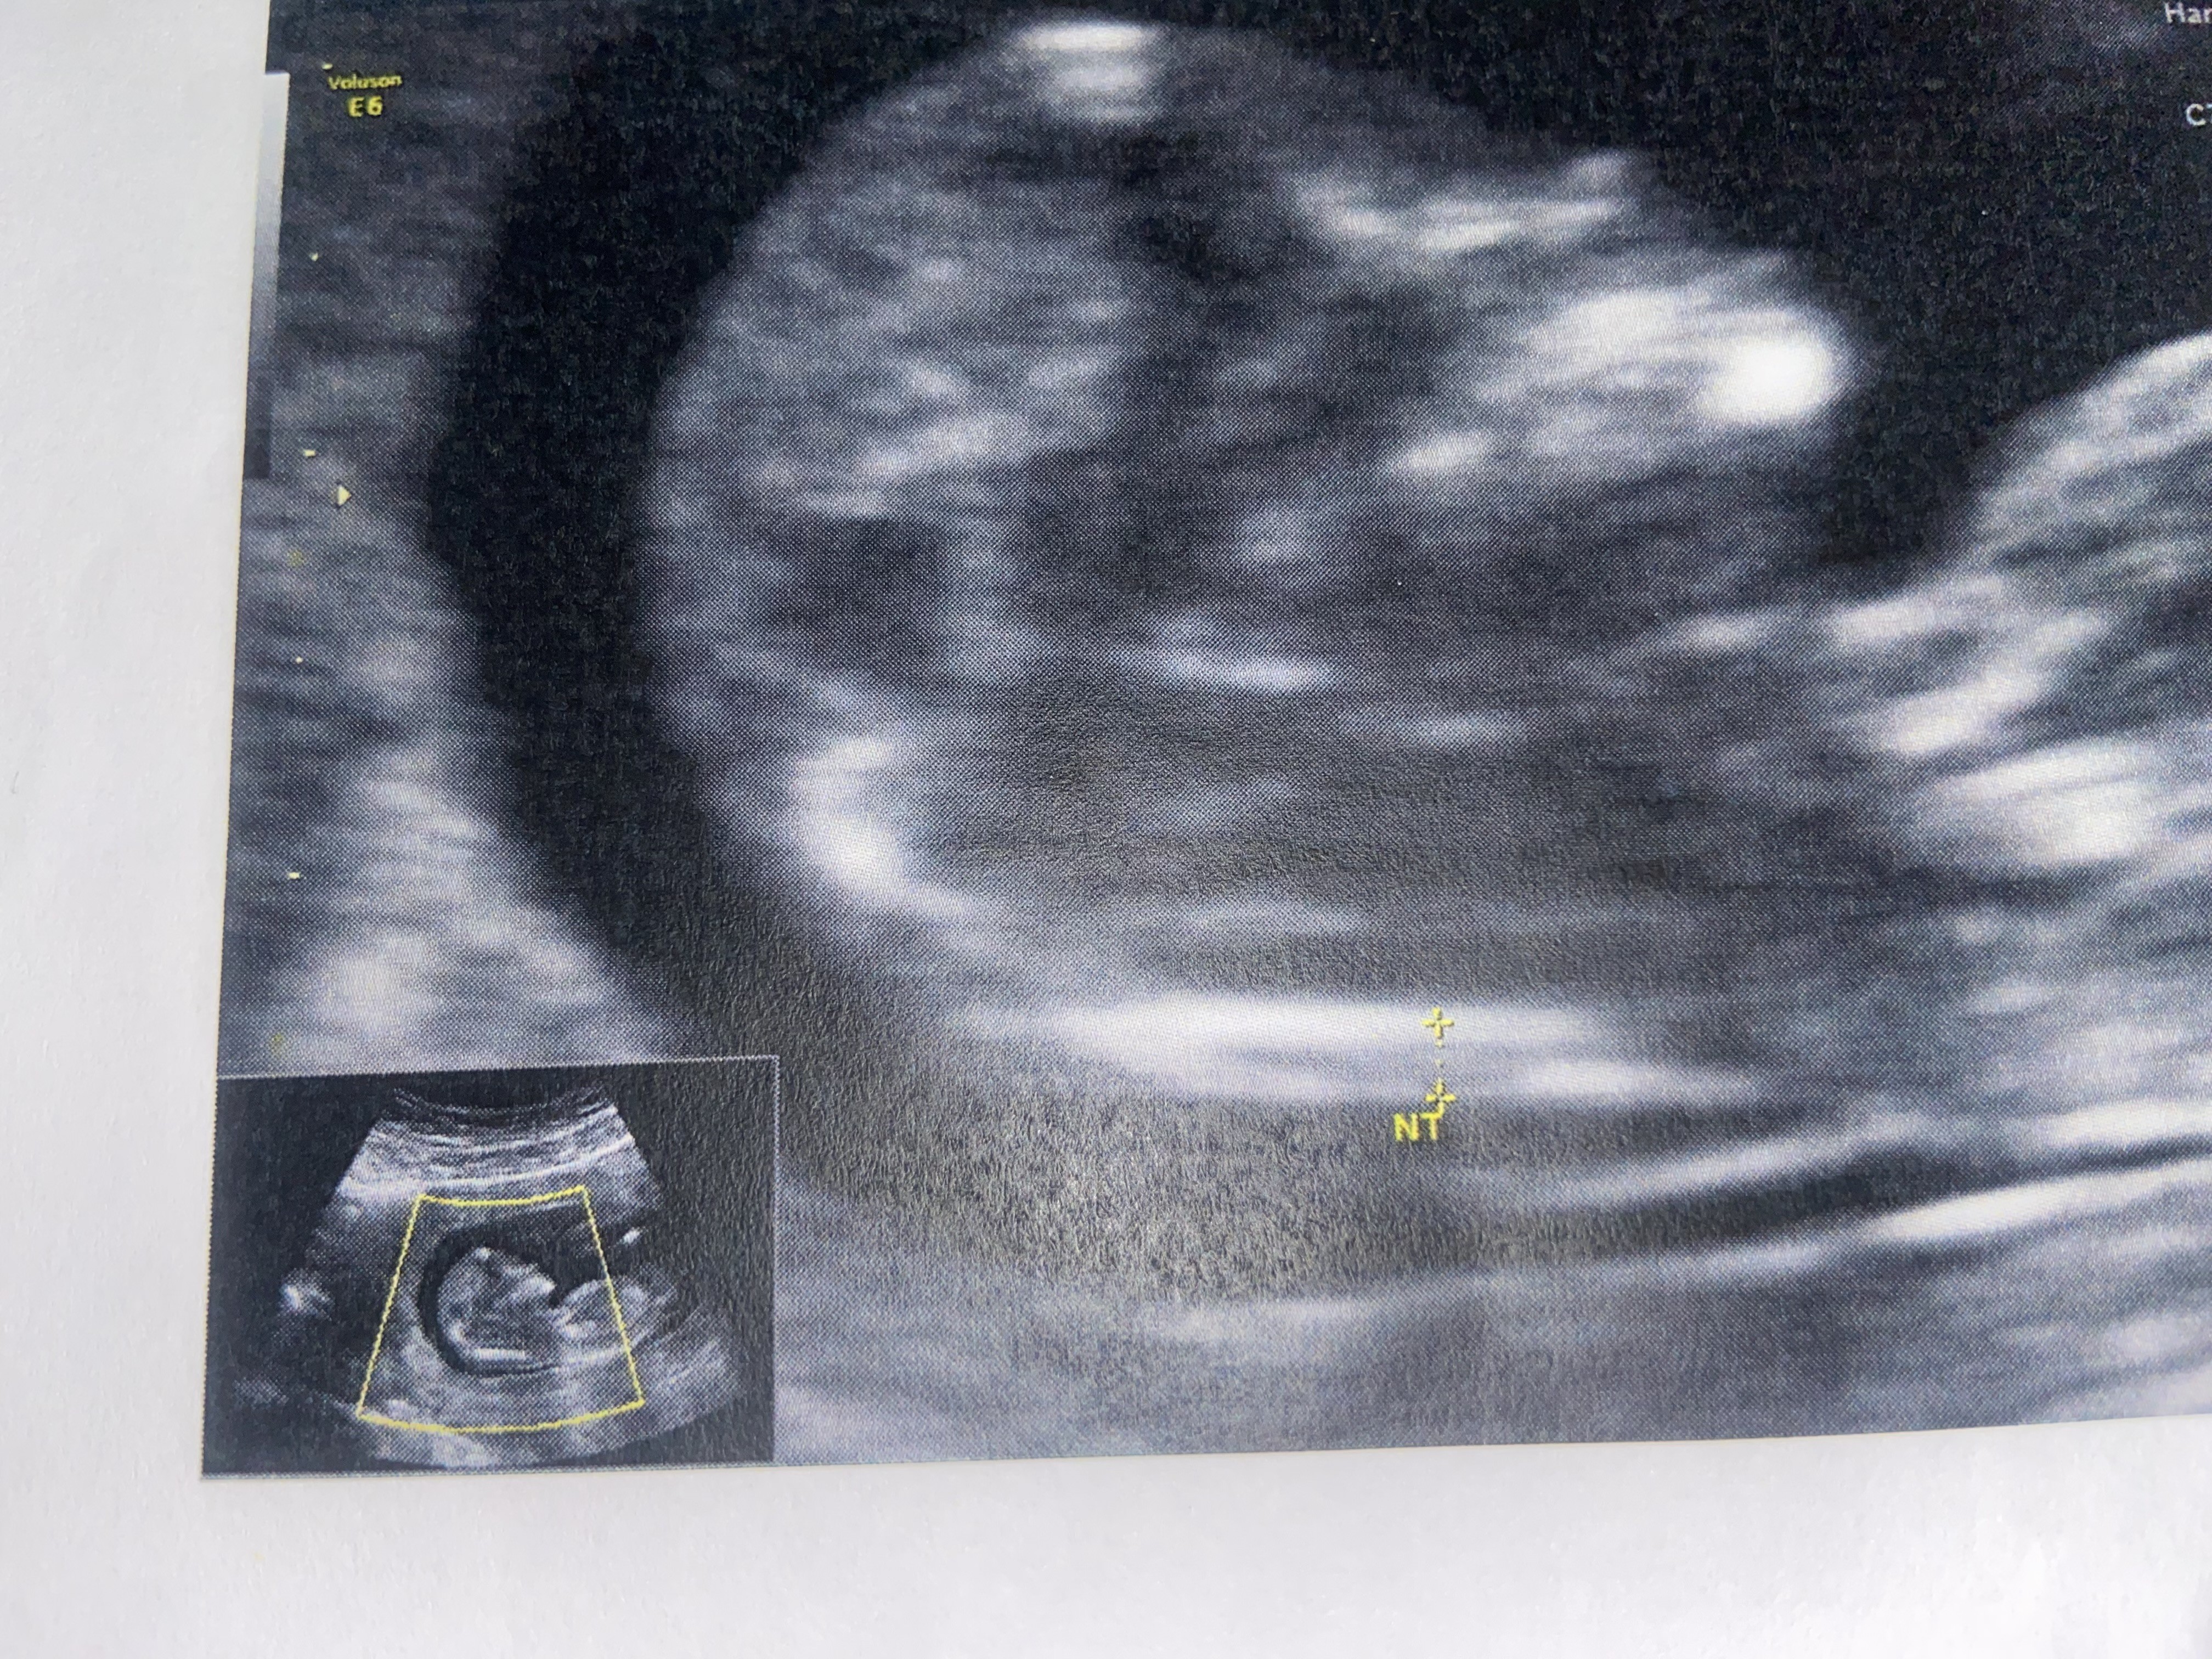

Gdybym nie miała wątpliwości bym nie pytała jak u innych.Uważam, że lekarz ma kompetencje i wiedzę. Wie co robi

Ja wypowiedziałam się. Napisałam to co myślę.Gdybym nie miała wątpliwości bym nie pytała jak u innych.

W drugiej ciąży ten sam lekarz mierzył całkiem inaczej, dlatego wróciłam do zdjęć z 1.